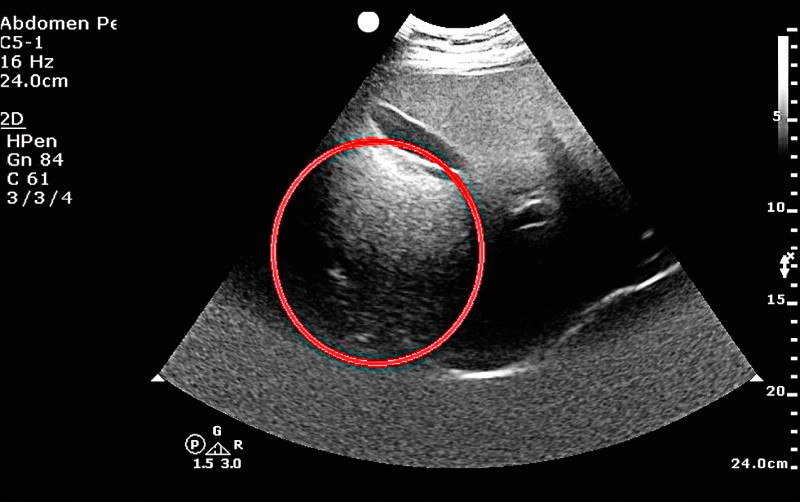

台中50歲林先生是B型肝炎帶原者,平時固定在診所抽血檢查追蹤,多年來數據正常,日前因血液中肝癌的腫瘤標記指數異常,轉介至醫院安排腹部肝臟超音波檢查,赫然在肝臟發現3公分大腫瘤,已是第2期肝癌,醫師提醒B型肝炎患者,要定期接受腹部超音波檢查,避免小病拖成大病。

台中50歲林先生是B型肝炎帶原者,平時有固定在診所抽血檢查追蹤,多年來數據都正常,直到日前因血液中肝癌的腫瘤標記指數異常,轉介至醫院進一步安排腹部肝臟超音波檢查,赫然在肝臟發現3公分大腫瘤,且已是第2期肝癌,醫師提醒B型肝炎患者,也要定期接受腹部超音波檢查,避免小病拖成大病。